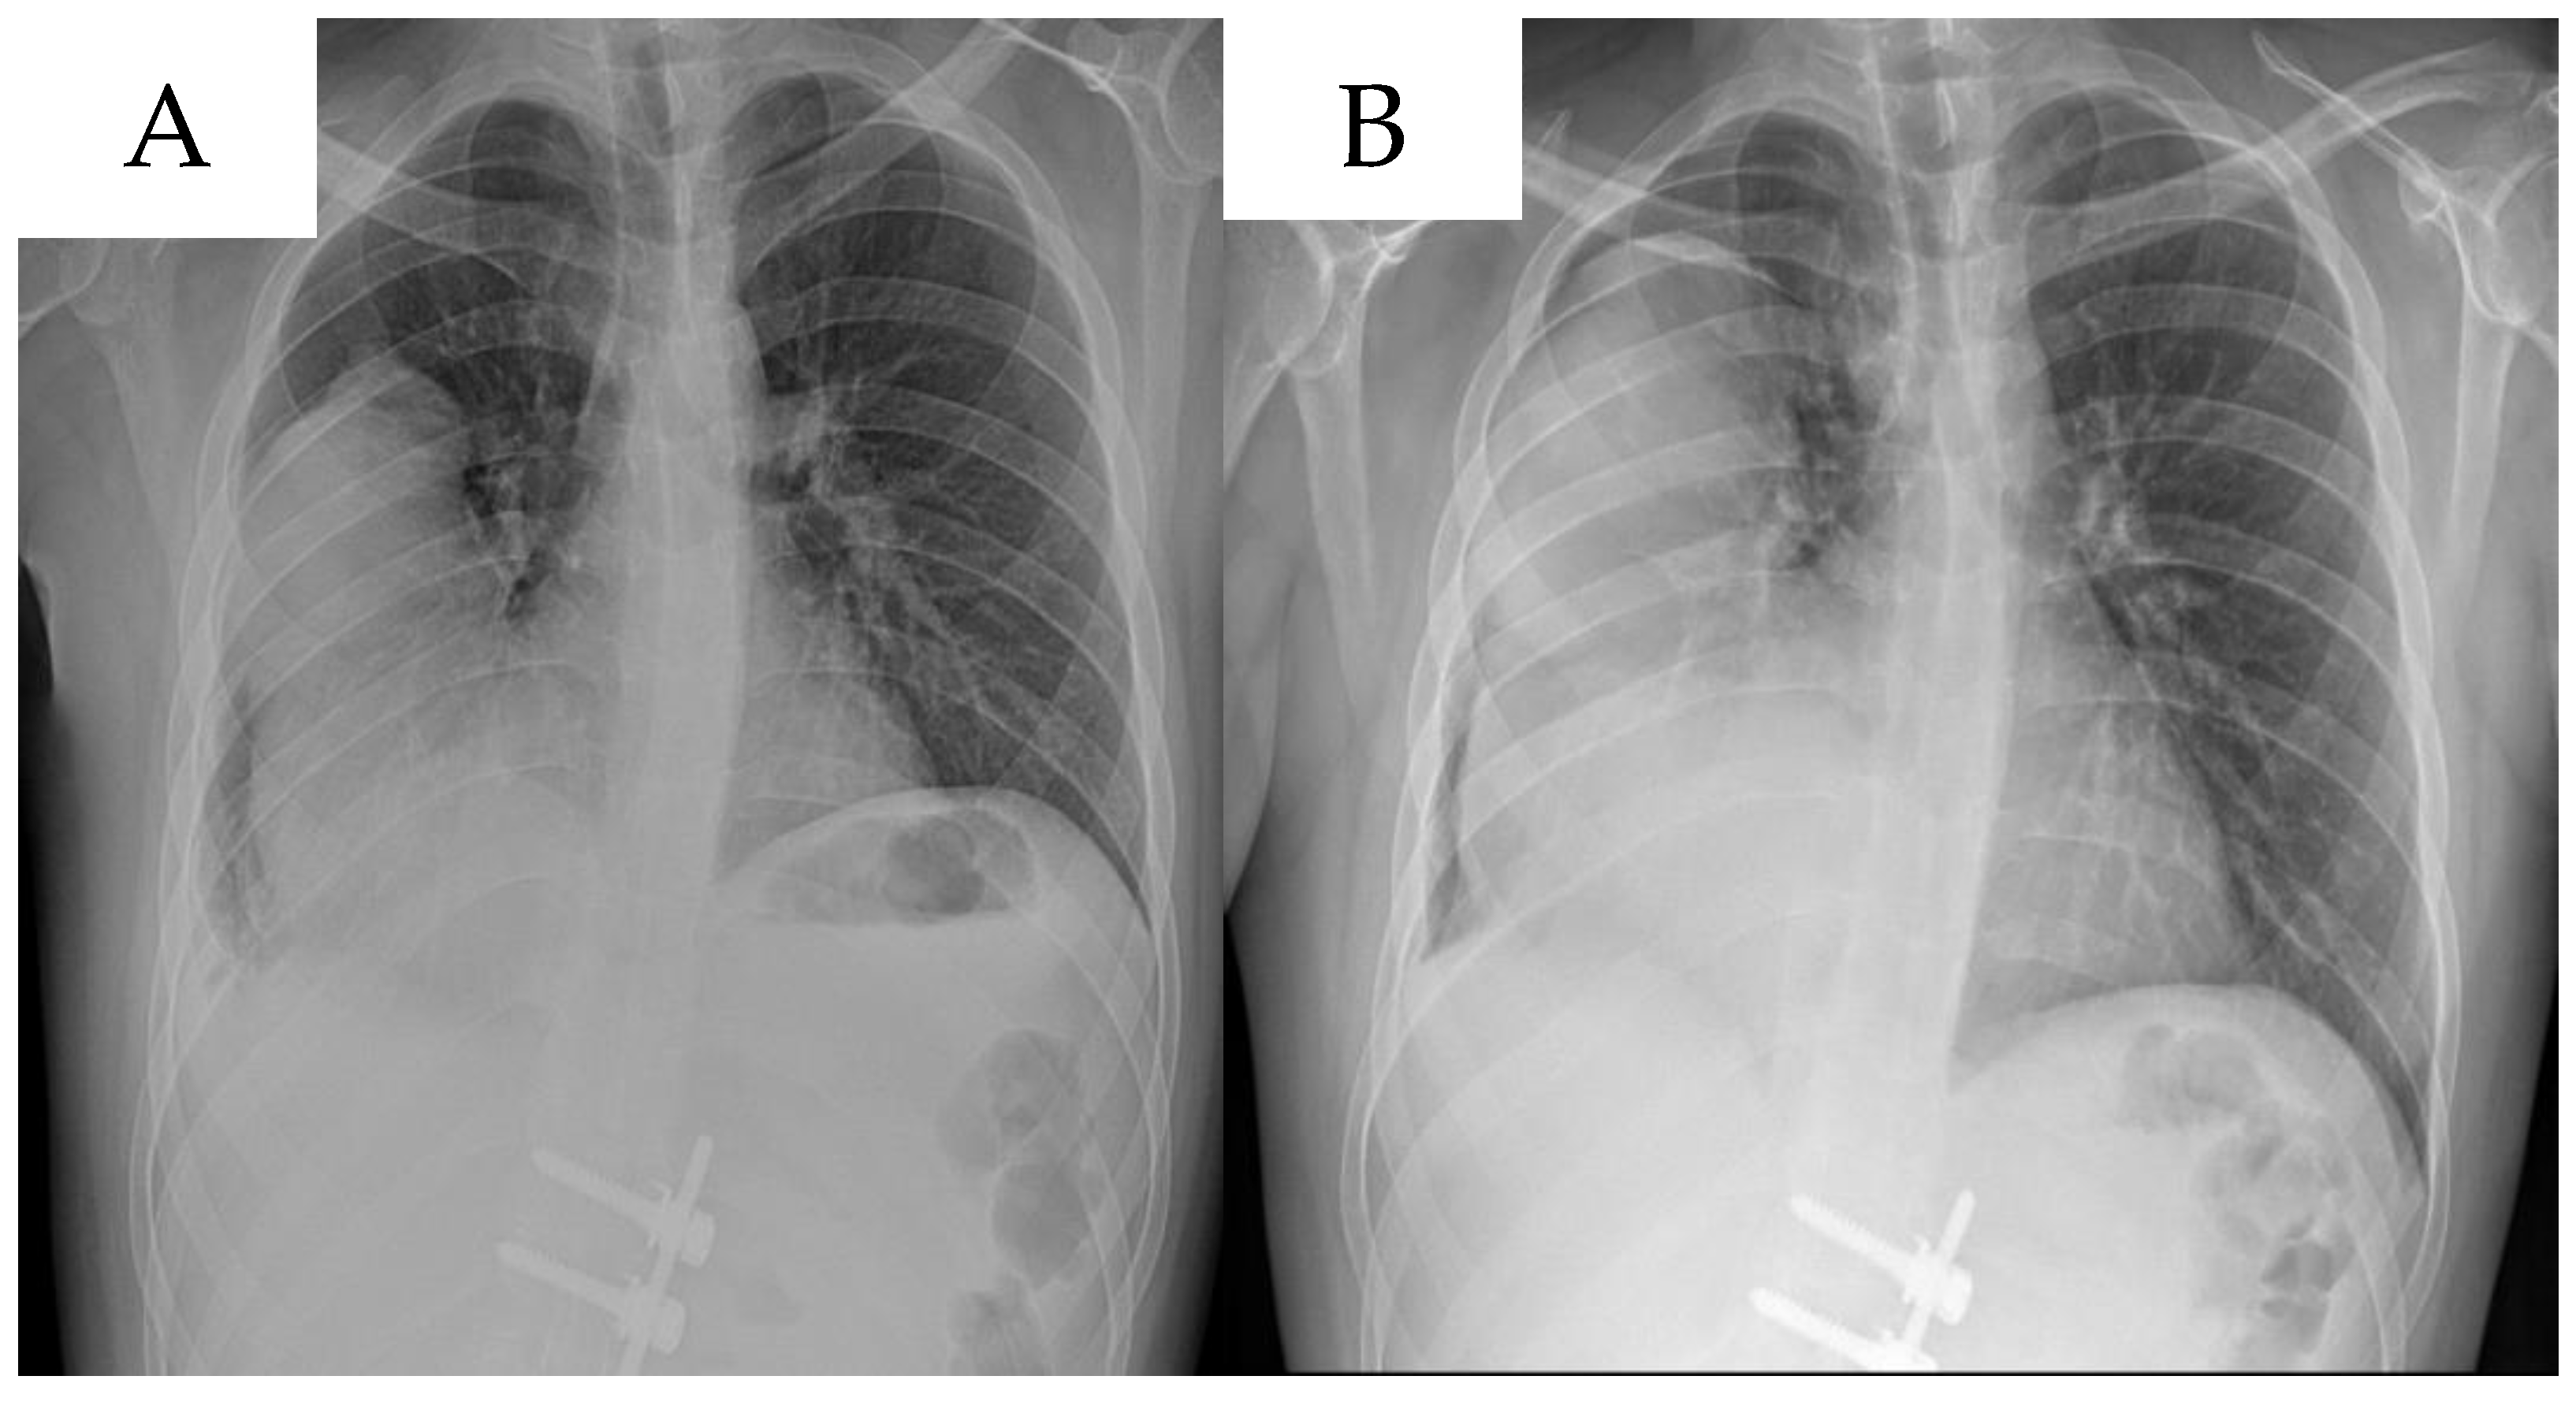

| 13 | Presented case | M/24 | Dyspnea, heartburn, intermittent tachycardia, right shoulder pain, expectoration of white sputum | Left lateral retroperitoneal region | 22 × 13 | Surgery, Trametinib treatment | NR |